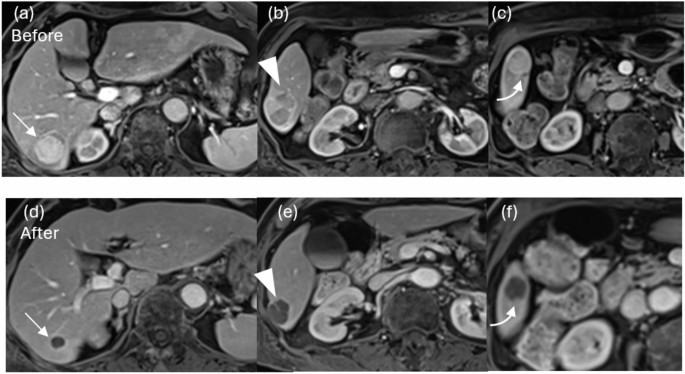

Arterial phase of contrast-enhanced MRI before (a, b, c) and after (d, e, f) BOAI-TACE in a 75-year-old man. Sixteen hepatocellular carcinomas (HCCs) were found in the liver, including a 32 mm HCC in S6 (a, arrow). The contrast effect of a 32 mm HCC in S6 disappeared after treatment and complete response (CR) was achieved (d). (b, e) A 22 mm HCC in S6 was also achieved CR (arrowhead). (c, f) An HCC in S5 (curved arrow) was also achieved CR. CR was obtained for the target lesions; however, there was a residual tumor in the non-target lesions and the overall evaluation was partial response.